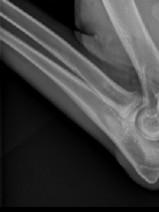

- décrire la présentation clinique des principaux cancers rencontrés dans l’espèce féline et les outils (biologiques, imagerie) indispensables de la démarche diagnostique ;